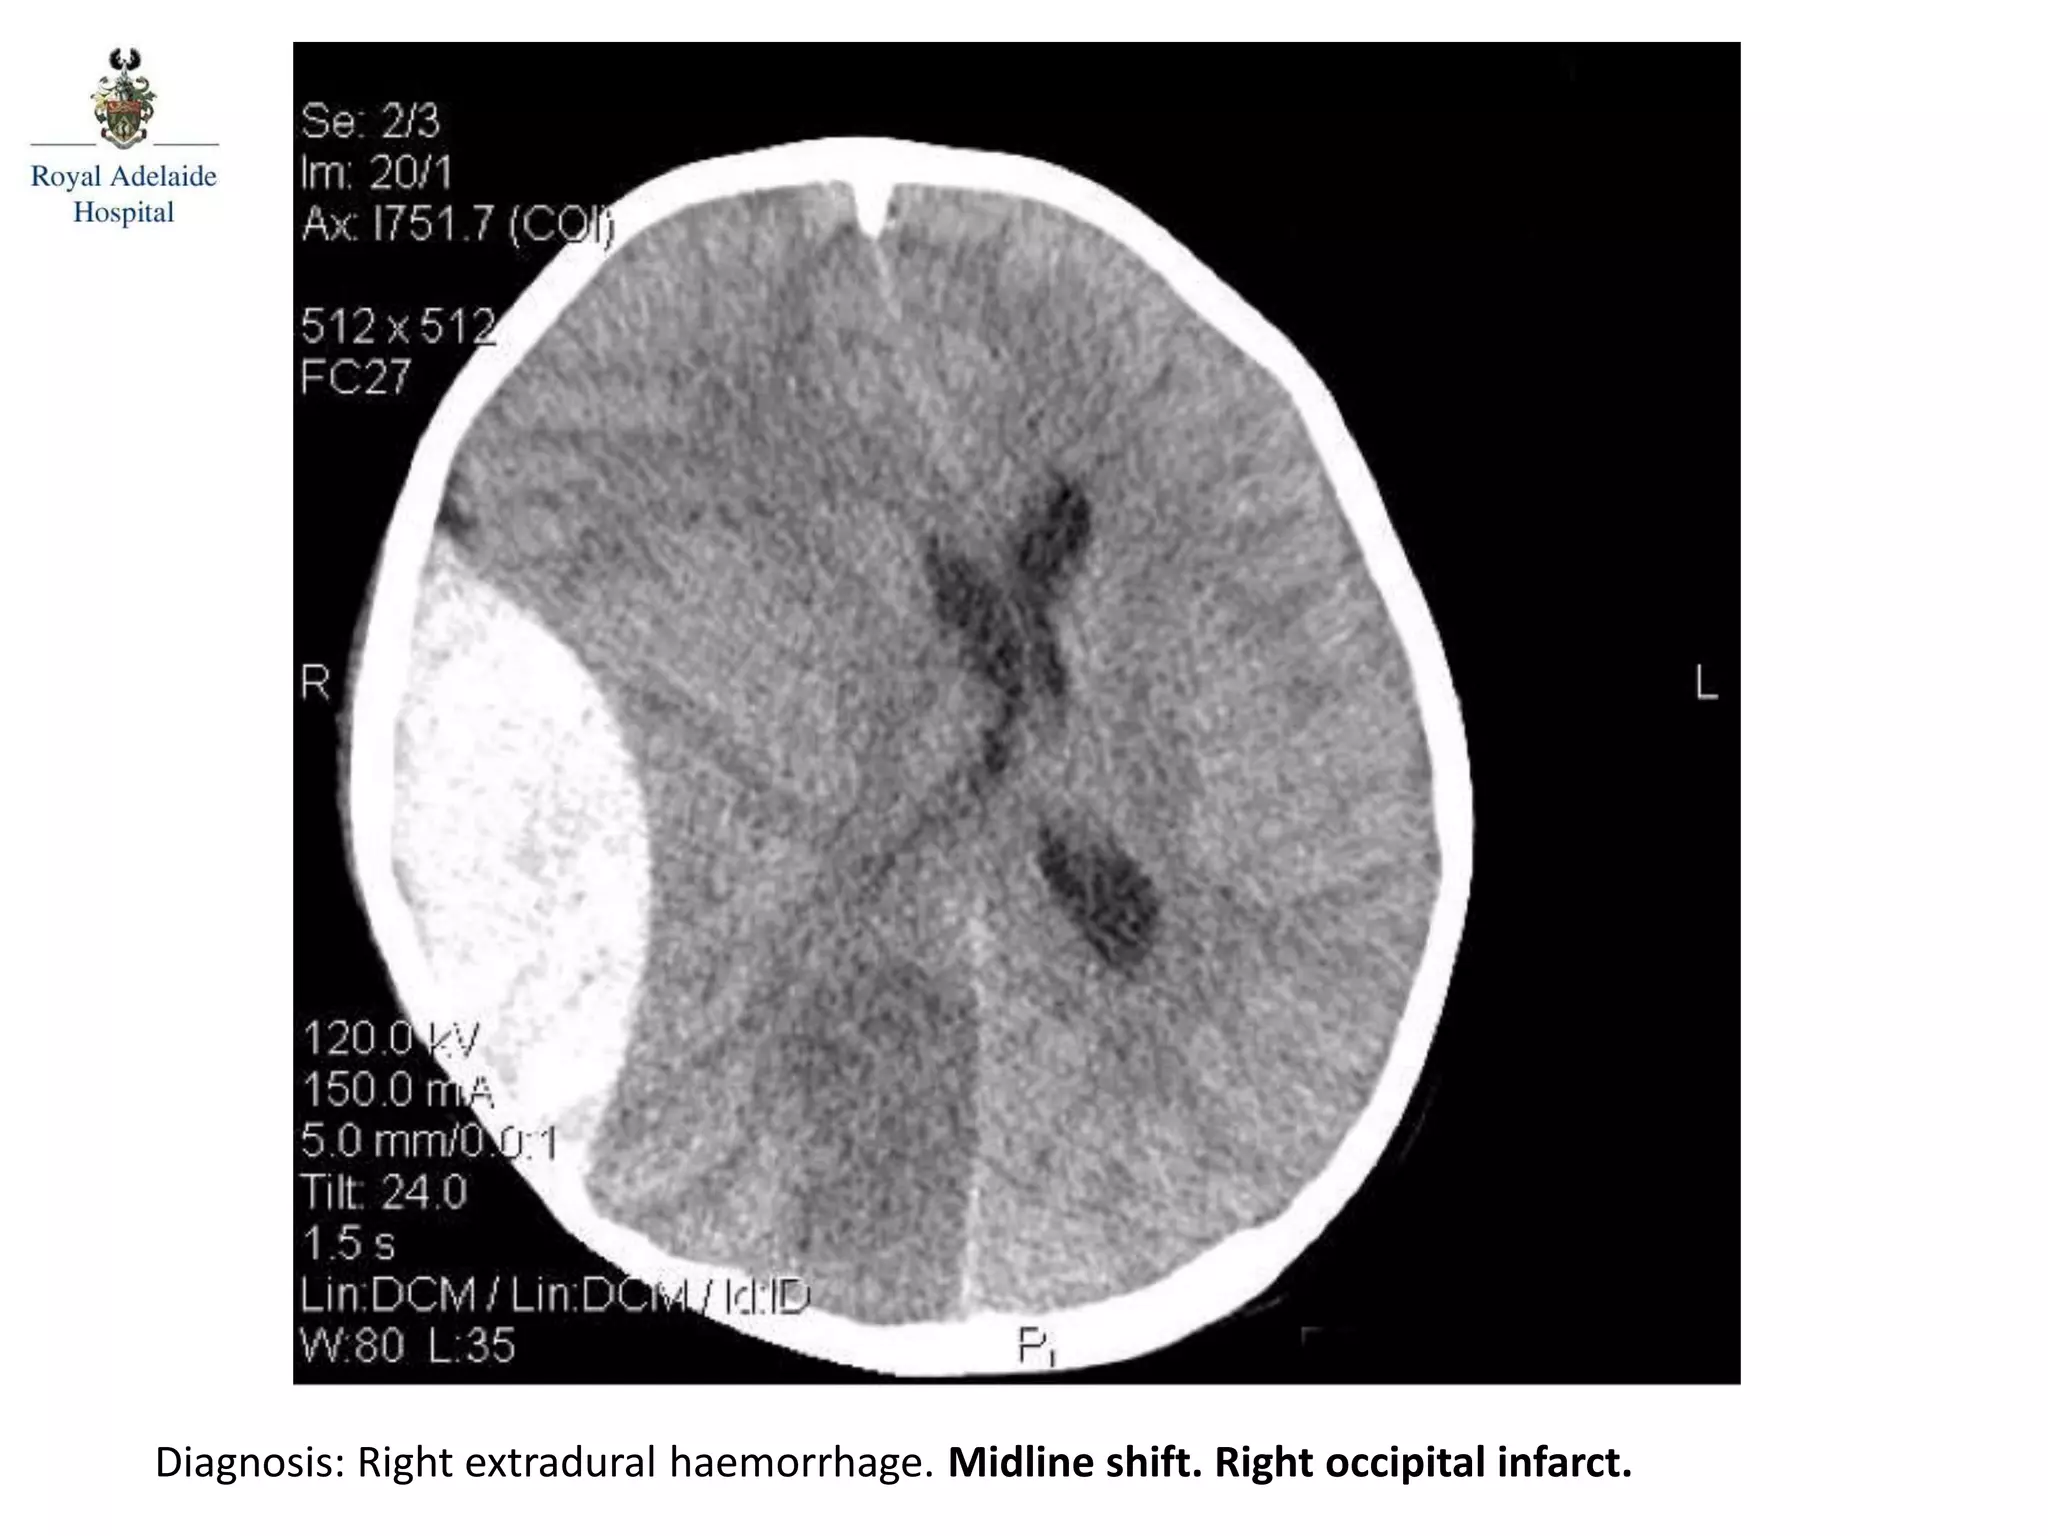

The document outlines multiple diagnoses from head CT cases, including small left basal ganglia bleed likely due to hypertension, various types of subdural and subarachnoid hemorrhages, and evidence of hydrocephalus. It details traumatic origins of some hemorrhages and notes obstructing masses and atrophic changes. Overall, there are significant findings indicating complications related to cerebral hemorrhages and ventricular enlargement.